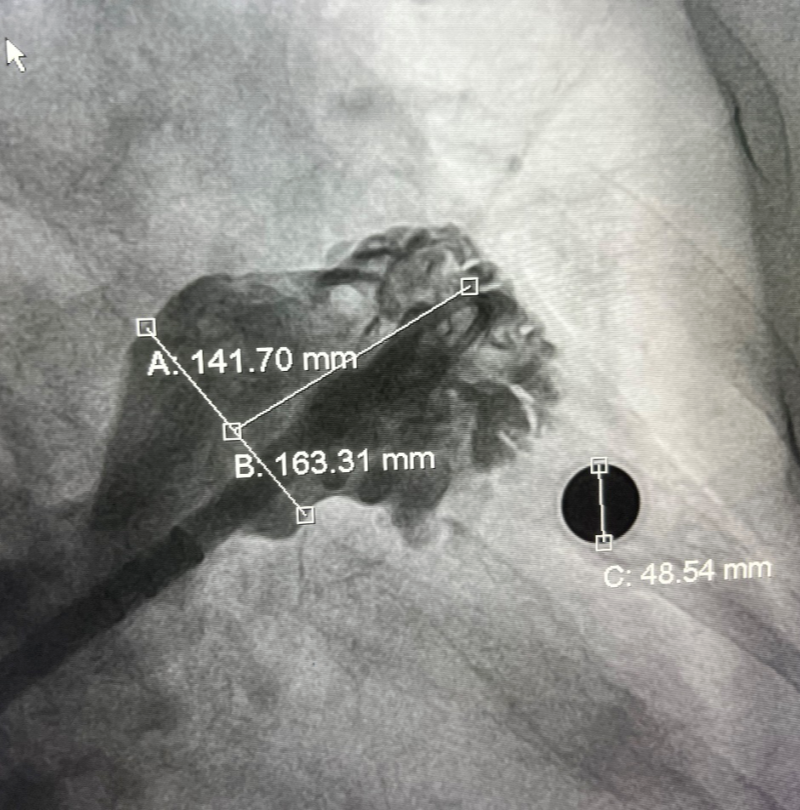

经过完善的术前CT和全面的Truplan软件术前分析准备。在介入室的全面配合下完成该患者的术前准备工作,谢桂庭进行房间隔穿刺,精准定位穿刺位点。行左心耳造影,造影结果显示开口28mm左右,深度32mm左右。结合术前Truplan结果以及术中DSA测量结果,选用WATCHMAN 33mm封堵器进行封堵。

在团队紧密配合下,谢桂庭巧妙地将封堵器坐落到心耳上缘囊袋,同时施加逆时针的力减少下缘露肩。缓慢平稳展开,一次到位,实现平口封堵。在DSA下进行牵拉实验,封堵器回弹明显无位移,提示稳定性良好。左心耳封堵器无露肩,无残余分流,压缩比13%-25%,满足PASS原则评估,释放封堵器。